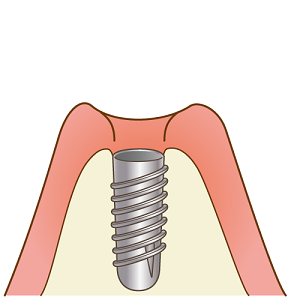

一次手術

インプラントを埋め込みます。